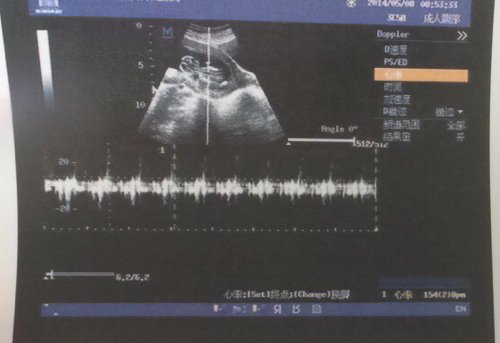

请问胎儿三个月,做b超头顶颅骨有个小缺口,是发育不全吗? 点击展开 匿名用户 2014-05-09 21:42 为您推荐: 其他回答 病情分析: 你好,这个问题考虑是可能的, 指导意见: 目前描述的情况我建议及时的定期检查,继续观察。 白其雨_6xwx 2014-05-10 09:13 相关问题 您好,我孕十三周零两天,刚才做B超时大夫说胎儿头颅还未发育完全,颅骨上还有一小缺口,请问这是否属于 怀孕五个月怎么阴道出血做B超说胎儿颅骨圆形光环完整,BPD5 7 FL3 8 羊水最深6 0 正常吗? 怀孕过了预产期六天,裤子上天天都有水果冻一样的是褐色的今天做了B超,胎儿颅骨光环完整,位于耻骨联合